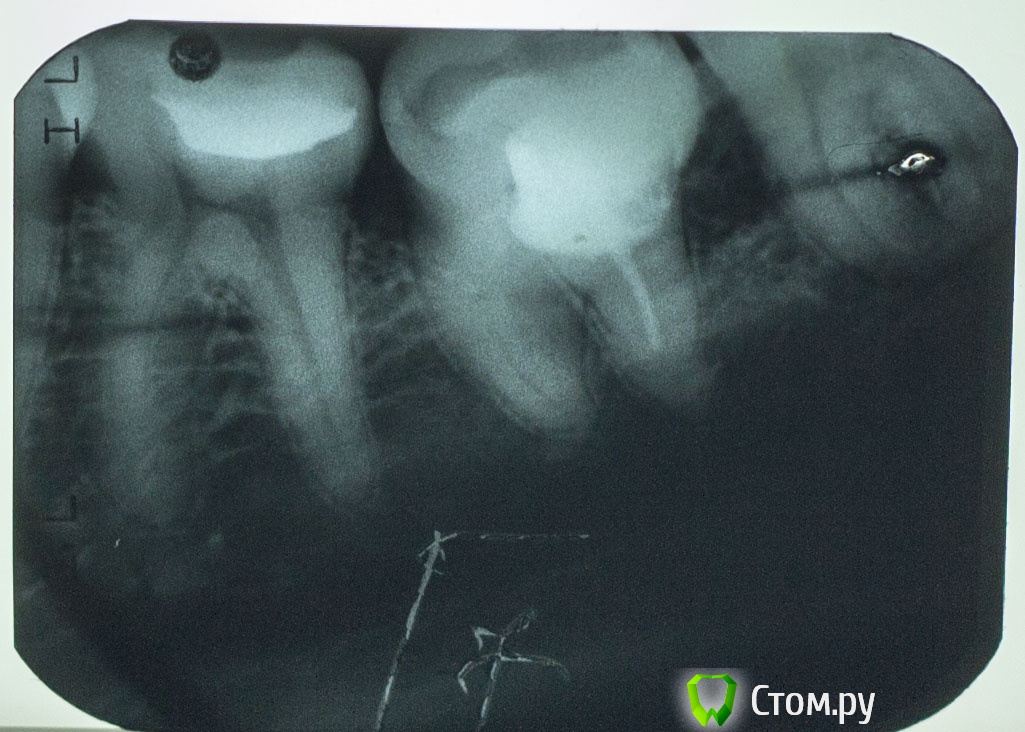

Vlad74 Опубликовано 15 января, 2014 Поделиться Опубликовано 15 января, 2014 Добрый вечер, прошу помощи. 2 месяца назад был пульпит, долго не могли определить какой зуб, ходил 2 недели в поликлинику. В итоге вроде нашли зуб 7 нижний (проводили электроодонтодиагностику показания 60, вроде бы немного болел при накусывании и постукивании), заложили мышьяк. Через 3 дня достали. Легче не стало. Через неделю болела вся левая половина верхней и нижней челюсти, наконец определили пульпитный зуб ( 5 сверху), в течении неск дней полностью запломбировали, 5 сейчас не беспокоит. Вопрос по 7 зубу. Снимок до лечения №1. Лечил в платном кабинете. Прочистили, запломбировали 1 канал, сказали остальные 2 непроходимы, поставили какую то пасту, неделю ходил с временной пломбой, боли не было. Далее поставили постоянную. После этого заболел зуб, сильная пульсация. Сделал снимок (№2), был в шоке как сделали. Через неделю обратился по гарантии. Вскрыли, заново прочистили 2 канала, поставили лекарство на неделю. Боли не было. Далее запломбировали 2 канала - 1 штифтами, 1 пастой. Сказали есть перфорации в коронковой части, заделали цементом. 3 канал не нашли, долго искали! Направили к другому врачу этой же клиники, по снимку определила ПЕРЕЛОМ корня зуба и однозначное удаление. Сейчас зуб под временной пломбой, часто напоминает о себе, реагирует на постукивание, при накусывании, немного на холод. Обратился еще к 2 стоматологам в другие клиники за советом, 1 сказал что перелома нет и нужно искать канал, 2 что каналы непроходимы и удаление. Текущий снимок №3. Пожалуйста, посоветуйте стоит ли пытаться продолжать лечение и что делать, если не найдут канал? ЗЫ Зуб значительно наклонен в сторону языка, боковая стенка зуба располагается примерно посредине жевательной поверхности соседних зубов. Спасибо Ссылка на комментарий